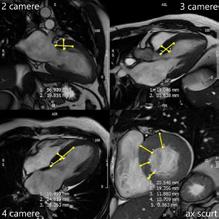

3. Rezonanța magnetică cardiacă

RMc oferă informații despre morfologia cardiacă, funcția ventriculară și caracteristicile miocardului ventricular[18]. Evaluarea prin această tehnică a pacienților cu CMH diagnosticată sau suspectată ar trebui făcută ținând cont de recomandările ghidurilor de specialitate și ar trebui realizată și interpretată de echipe cu experiență în imagistica cardiacă și în evaluarea cardiomiopatiilor.

RMc reprezintă standardul de aur pentru cuantificarea volumelor și maselor ventriculare, fibrozei și a fracției de ejecție. Evaluarea globală și regională a funcției contractile a VS, distribuția și extensia hipertrofiei și a fibrozei, anatomia și fiziologia VM – sunt elemente cheie în stabilirea unui diagnostic cert, a prognosticului și pentru elaborarea planului terapeutic. Astfel, RMc ar trebui efectuată încă de la evaluarea inițială. Despre morfologia și funcția VS, la pacienții cu fereastră ecocardiografică bună, se pot obține informații similare prin cele două tehnici[19]. Dacă anumite segmente ventriculare sunt greu vizualizabile, cum ar fi peretele antero-lateral sau apexul VS și VD, imagistica prin RM poate aduce informațiile lipsă, necesare diagnosticului[20]

Măsurarea masei ventriculare stângi are acuratețe superioară dacă este realizată prin RMc, care are o rezoluție spațială excelentă, dar este notabil că masa ventriculară stângă totală se corelează slab cu grosimea maximă a peretelui ventricular și poate fi normală la pacienții cu hipertrofie asimetrică, mai ales când hipertrofia interesează mai puțin de două segmente ale VS[19].

Ecocardiografia 2D poate să nu detecteze întotdeauna anevrismele apicale[21], trombii intracavitari[22], criptele miocardice sau anomaliile mușchilor papilari[23], imagistica radiomagnetică fiind o investigație mai sensibilă.

Tot imagistica radiomagnetică este utilă în evaluarea pacienților înainte de miectomia septală și poate îndruma atitudinea terapeutică deoarece poate descrie anumite caracteristici care sunt relevante pentru strategia chirurgicală, incluzând distribuția precisă a hipertrofiei septale (Fig.4), anomalii ale VM și ale aparatului subvalvular, poziționarea anormală a mușchilor papilari,

conexiuni aberante ale cordajelor, cât și anomalii ale căii de ieșire din VD. RMc poate fi folosită, utilizând proprietățile magnetice intrinseci ale țesutului miocardic și distribuția substanței de contrast pe bază de gadoliniu, pentru a detecta zonele de fibroză de la nivelul interstițiului miocardic. Captarea tardivă a gadoliniului (LGE) este utilizată pentru a diferenția miocitele normale, arhitectura acestora și ariile de fibroză. Din cauza heterogenității CMH, au fost descrise multiple modele de captare tardivă a gadoliniului: LGE subendocardică, transmurală, difuză. La 65% din pacienții cu CMH, LGE este prezentă având în mod tipic o distribuție neuniformă în zonele de hipertrofie care tind să se coreleze cu zonele de anomalii de contractilitate parietală. Fibroza este localizată mai ales în treimea medie a VS, având o distribuție multifocală, însă și VD poate fi implicat.

Extensia LGE este un marker al anomaliilor de deplasare ale pereților ventriculari și este asociată cu creșterea rigidității miocardice și cu remodelarea ventriculară avansată. Aprecierea gradului de fibroză septală prin identificarea LGE, poate fi utilă în alegerea conduitei terapeutice, înaintea tratamentului invaziv al înlăturării obstrucției din TEVS[24]

În câteva studii s-a documentat faptul că pacienții cu LGE au tendința de a avea un prognostic mai nefavorabil față de cei la care LGE nu se evidențiază[25].

Fig.4. Cuantificarea exactă a distribuției și dimensiunilor hipertrofiei septale în diferite secțiuni de rezonanță magnetică cardiacă.